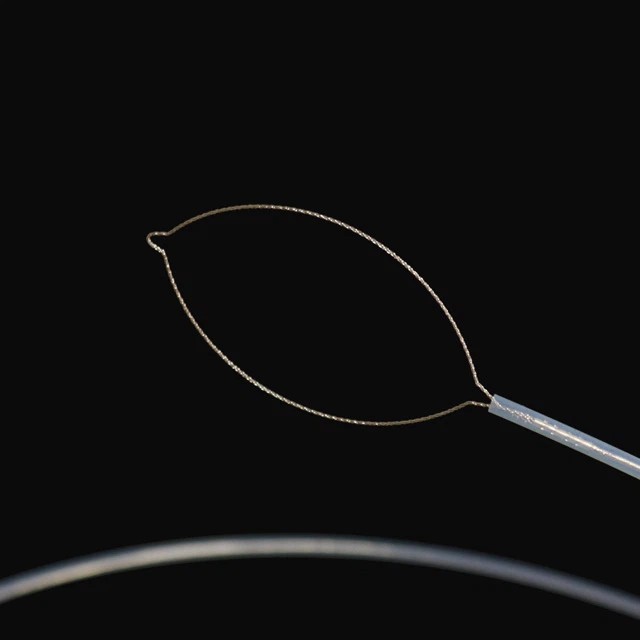

Postympuj zorty

FG{OR |

2.6 |

Srogsze aniżeli abo rōwne 2,8 |

2300 |

25 |

Owalny z necym |

|

FG{OR |

2.6 |

Srogsze aniżeli abo rōwne 2,8 |

2300 |

30 |

Owalny z necym |